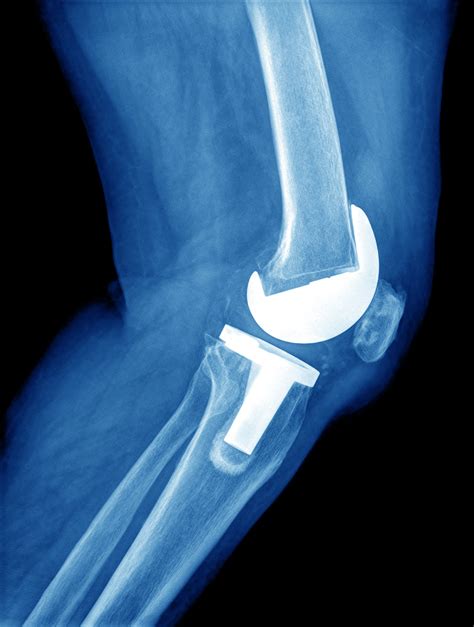

Knee replacement images play a crucial role in the diagnosis, planning, and execution of knee replacement surgery. These images provide valuable insights into the condition of the knee joint, helping surgeons to make informed decisions. Here are some key points about the importance of knee replacement images:

• Diagnostic Tool: Knee replacement images, such as X-rays, MRIs, and CT scans, help diagnose the extent of damage to the knee joint. These images can reveal bone spurs, cartilage loss, and other abnormalities that indicate the need for surgery.

• Preoperative Planning: Surgeons use knee replacement images to plan the surgical procedure. By studying the images, they can determine the size and type of implants needed, as well as the best approach for the surgery.

• Educational Resource: Knee replacement images are also valuable educational tools for patients. They help patients understand the condition of their knee joint and the steps involved in the surgical procedure.

Here is an example of how knee replacement images can be used in preoperative planning:

Here is an example of knee replacement images that illustrate the surgical procedure:

Knee Replacement Procedure